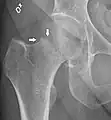

![]() | |

| Intertrochanteric hip fracture in a 17-year-old male | |